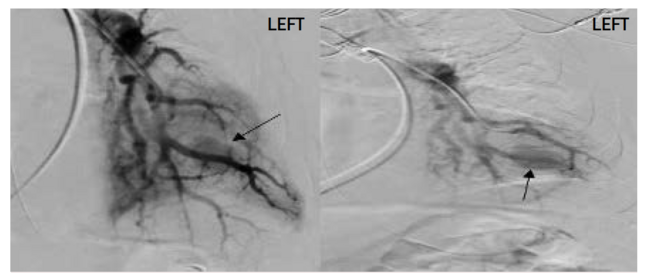

Based on CTA, the interventional radiology (IR) team was consulted, and they performed a pulmonary angiography. A large pseudoaneurysm arising from a left lower lobe segmental pulmonary artery branch was found (Figure 1), and it was successfully embolized (Figure 2).

On postoperative day (POD) 1, the patient was generally improving on minimal ventilatory settings, hemodynamically stable, and the anemia was improving. Respiratory cultures taken earlier via bronchoscopy were all negative. On POD 2, the patient was successfully extubated, the anemia improved to better than baseline, and the patient was transferred from the ICU to the hospital medicine service. On POD 3, a CT chest scan with and without contrast showed mild interval improvement in the left lower lobe consolidation without active contrast extravasation or pooling of contrast on arterial or delayed imaging. This supported the absence of residual pseudoaneurysm, and the patient was discharged on POD 5.